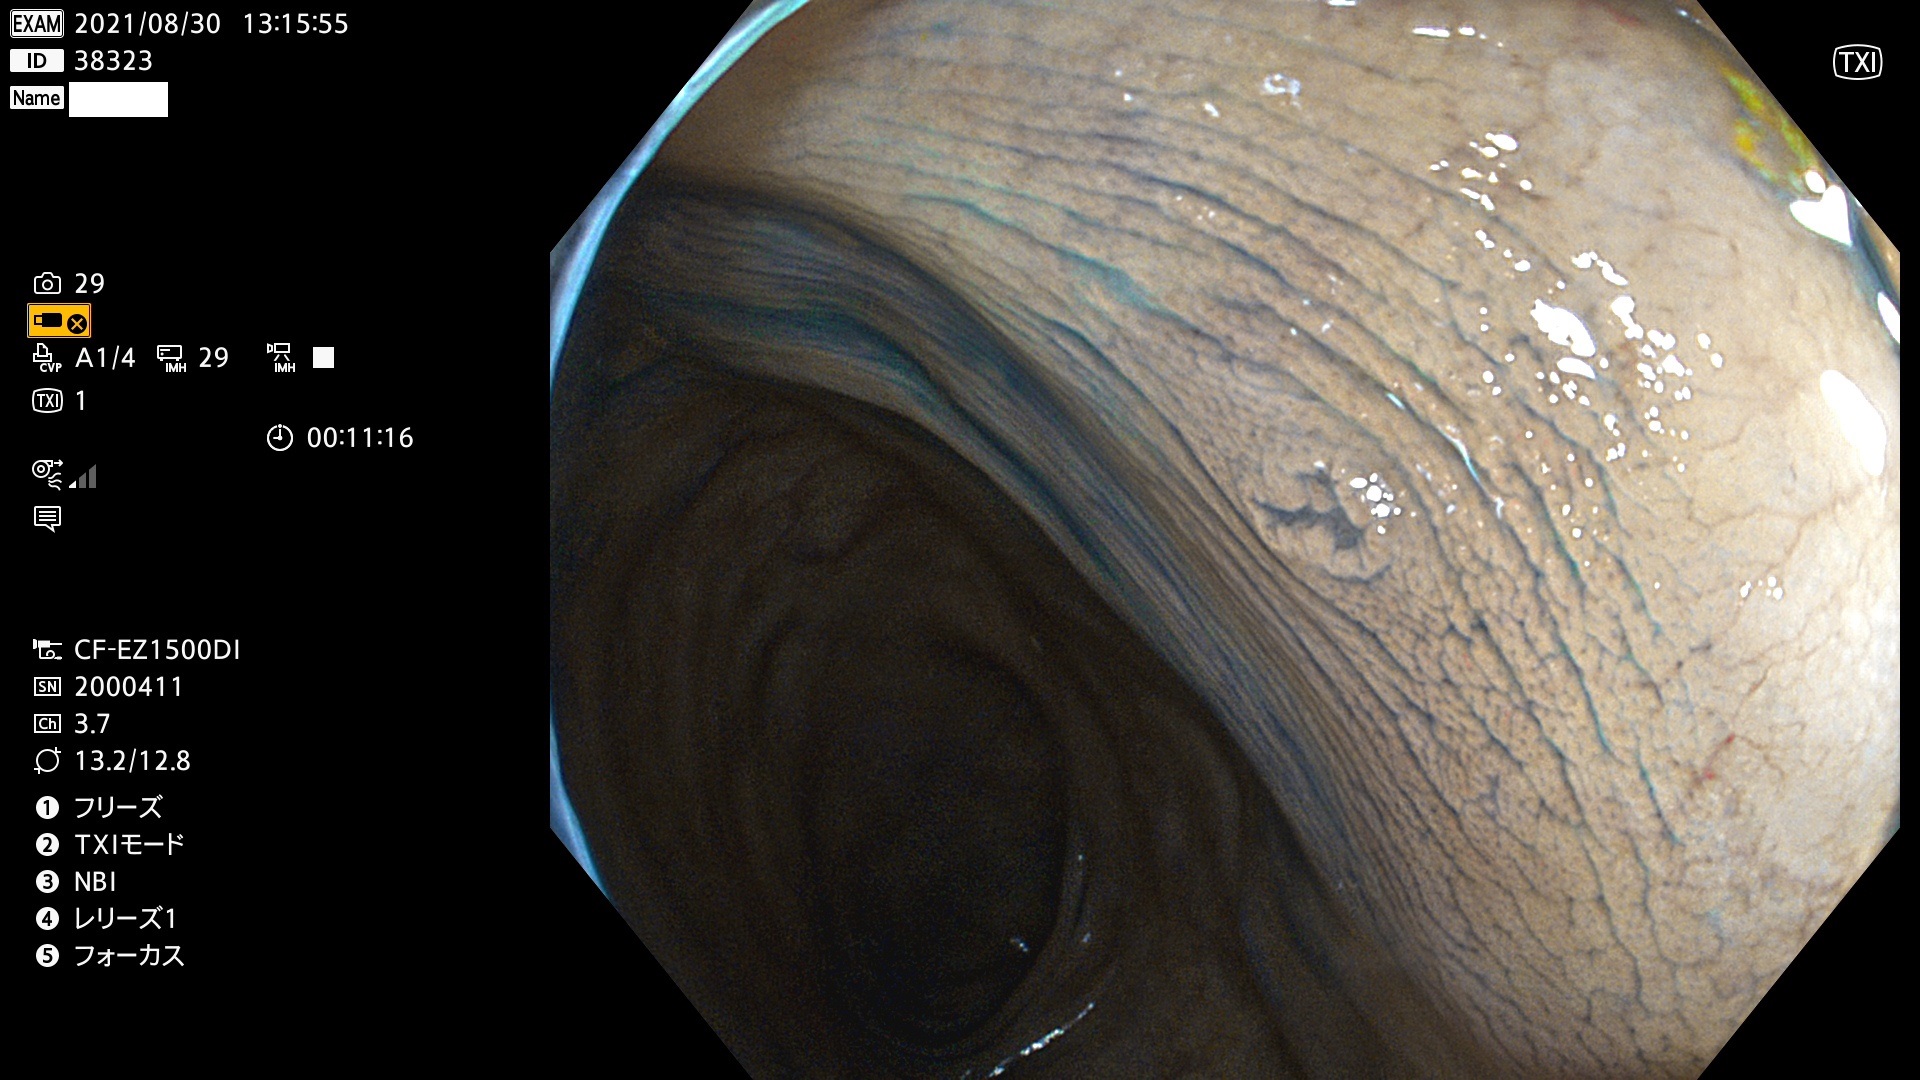

38300 38301 38302 38303 38304 38306 38307 38308 38309 38310 38311 38312 38313 38314 38315 38316 38317 38319 38321 38322 38323 38324 38325 38327 38331 38332 38333 38334 38337 38338 38339 38340 38341 38343 38346 38348 38349 38350 38351 38352 38353 38354 38355 38358 38359 38360 38361 38362 38363 38365 38366(SSAP) 38368 38369 38370 38371(SSAP) 38372 38374 38375 38376 38377 38378 38380 38381 38382 38383 38384 38385 38386 38388 38389 38391(SSAP) 38395 38397 38399

発見困難で危険性の高い平坦型病変(上記100名より抽出)